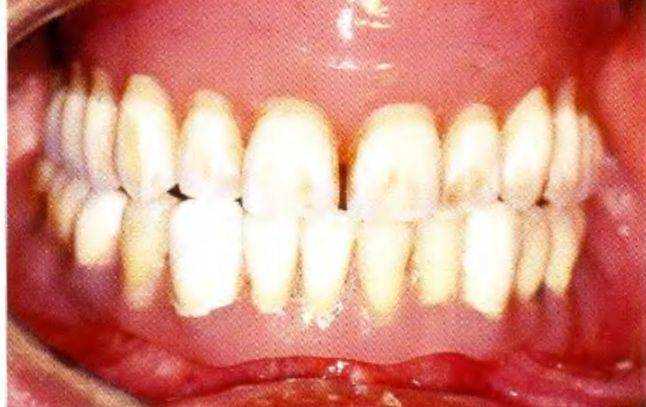

Выполненные манипуляции позволили обеспечить высокую ретенцию протезов и провести пациенту празднование 75-го дня рождения (рис. 1-9kk). Окончательный план лечения включал в себя изго-

Рис. 1-9kk. Выполнение поставленных задач - обеспечена высокая стабильность съемных протезов